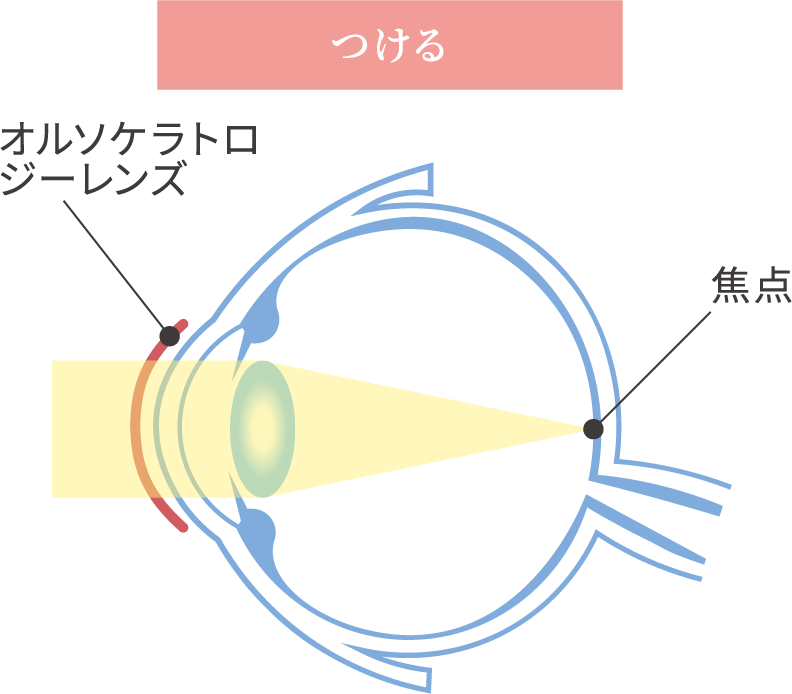

生活習慣へのアドバイスから点眼・コンタクト治療まで

近視は幼児期、学童期、思春期を通し、主に眼の長さが伸びることで、焦点の合う距離が近くなり、焦点距離が近くなればなるほど遠くの像がぼやけてしまいますので、視力が低下します。

近視にはもともと備わっているピント調節機能が関わっています。

眼は近くを見るときには調節力を使ってピントを合わせています。

目にする対象物が近い距離にあればあるほど、この調節力を強く使わなければなりません。

これが問題となり以下の機序が働き、近視は発症し、進行すると考えられています。

- 軸外収差

- 目の中に入ってきた像を網膜が感じ取りますが、

網膜の中心から少し離れた場所におこるぼやけのこと